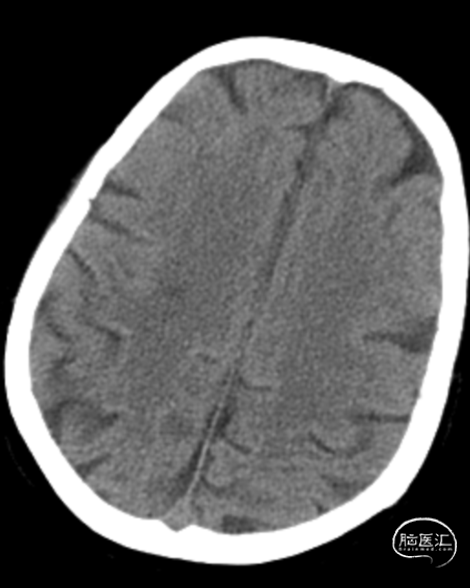

术前影像学检查

➢术前CTA

➢术前DSA

➢术前CTP

➢术前HMRI

➢术后次日CT

➢术后1周CTP